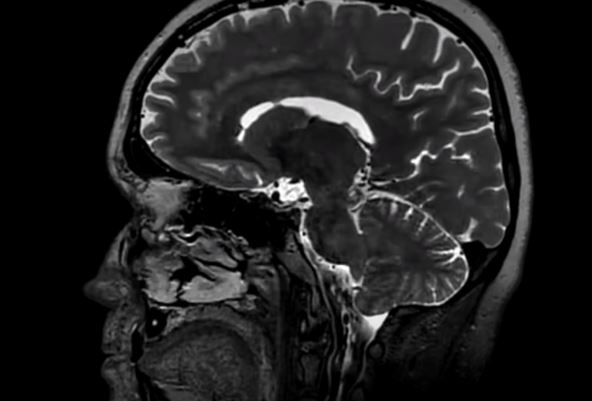

Urađene su mu sve moguće analize, i zbog straha od neurološkog problema, doktori su uradili i skener mozga. Na slici su ugledali jeziv prizor - nekoliko pantljičara se nastanilo u mozgu pacijenta. Ovo stanje naziva se cerebralna cisticerkoza, i nastaje kada se paraziti uneti kroz hranu, najverovatnije nedovoljno termički obrađeno meso svinje, nastane u mozgu.